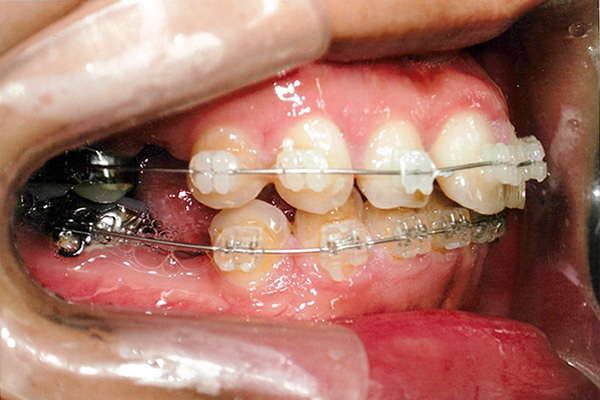

10ヶ月後